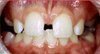

DİASTEMA

Diş eksikliğinde, dişlerdeki boyutsal oransızlıklarda görülebilir. Estetik ve konuşma problemine yol açabilir.